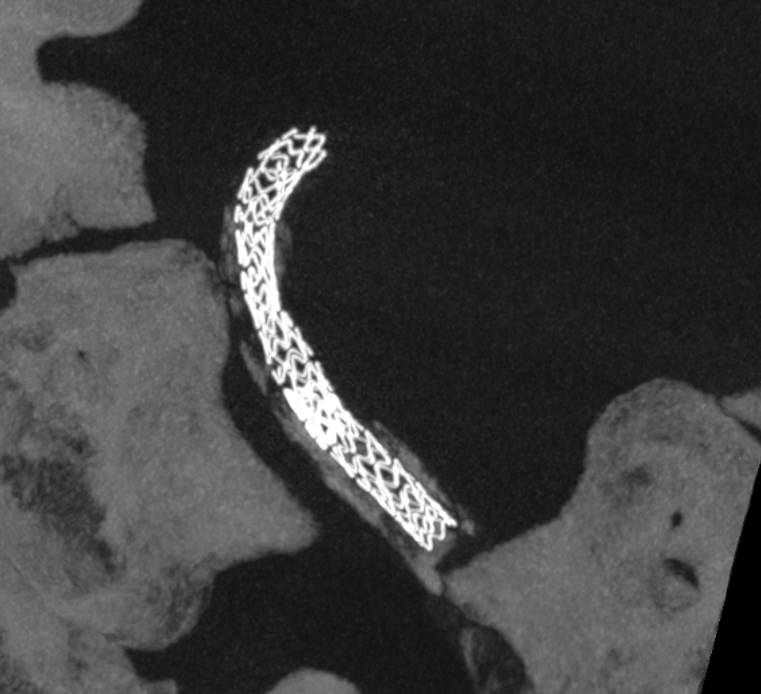

“Dry” noncontrast Vaso-CT (22 cm FOV protocol, 20 seconds acquisition, reconstructed with 50% FOV and 5123 matrix), showing the stents in the artery and the calcific plaques.

Laser-cut balloon-mounted stents make it easier to leave the PICA alone – critical given what you see below. The best choice in our opinion.